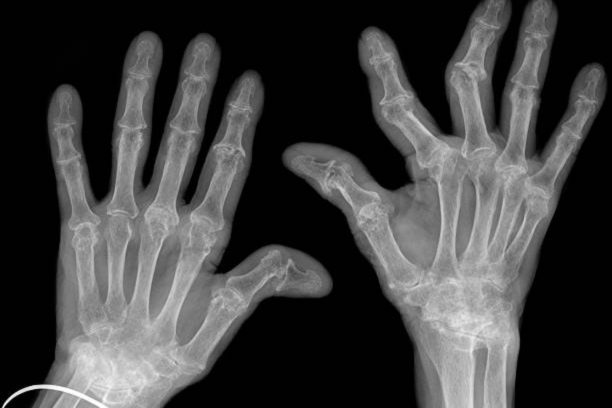

Introduction Rheumatoid Arthritis (RA) is a chronic autoimmune disorder that primarily affects the joints, causing pain, inflammation, and impaired mobility. […]